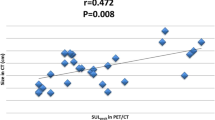

FDG PET/CT response was determined by a different physician certified in both radiology and nuclear medicine (CCR). The reader was aware of the clinical diagnosis but blinded to clinical follow-up information. For all target lesions identified by the reader, peak standardized uptake values normalized to lean body mass (SULpeak) were determined [14] (PET-VCAR AW Suite 2.2, Advantage Workstation, GE Healthcare). In a separate analysis, we evaluated response classifications based on the clinically more commonly used maximum standardized uptake values (SUVmax) and compared these to response classifications based on SULpeak. Selection of lesions and response categorization was based on PERCIST as summarized in Table 1 [14].

Changes in SULpeak and SUVmax were very closely correlated (r = 0.998). Consequently, the response classification (CR, PR, SD, or PD) was the same when SUVmax was used instead of SULpeak. Response categorizations as assessed by CE-CT and FDG PET/CT are summarized in Table 3. Overall, there was only fair to moderate agreement between response assessment by CE-CT and FDG PET/CT (kappa = 0.36, weighted kappa = 0.45). However, all 22 patients categorized as CR or PR by CE-CT were also categorized as CR or PR by PET/CT. In contrast, marked differences in response assessment were observed for the 43 patients categorized as SD or PD by CE-CT. Seventeen (40%) of these patients were classified as PR or CR by PET/CT (Table 3, Fig. 2). Of the 15 patients classified as PD by CE-CT, 3 were classified as CR by FDG PET/CT, 1 as SD, and 11 (73%) concordantly as PD. All three patients with discordant CR on PET/CT had new or progressive bone lesions on CE-CT. The 28 patients categorized as SD by CE-CT were classified by FDG PET/CT as CR in 6 cases, as PR in 8 cases, as PD in 6 cases (Fig. 3 ) and, concordantly, as SD in only 8 cases (29%). Of the 24 patients without osseous involvement, 9 (38%) had SD on CT and 2 (8%) had SD on PET/CT. Only two of the nine patients without osseous involvement and SD by CE-CT were also classified as SD by FDG PET/CT (one was categorized as CR, two were categorized as PR and four as PD; see Table 4 for details).

Tumor FDG uptake can be measured in various ways, including SULpeak and SUVmax, raising the question of which parameter is most suitable for response assessment. We have used SUVmax in a preliminary analysis of our data, which showed very similar differences in PFS and DSS between responders and non-responders [26]. In the present study, the response classification was unchanged when SUVmax was used instead of SULpeak for response assessment. This suggests that response assessment by PERCIST is not significantly affected by differences in SUV quantification, which is encouraging for its broader clinical use.